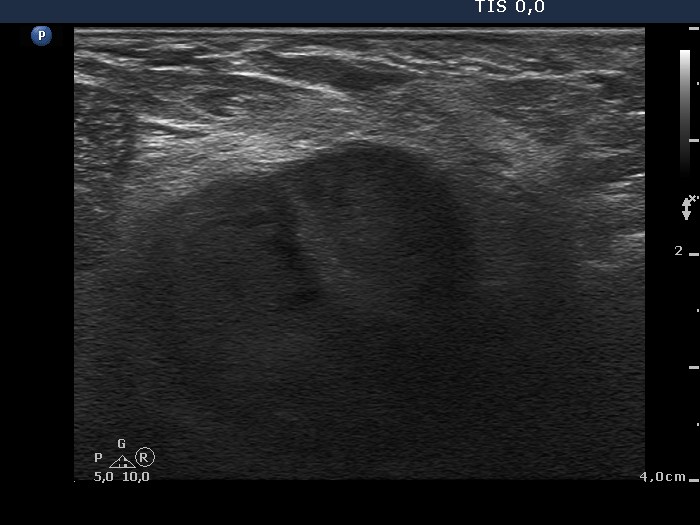

The borders of the nodule - case 1481 (ultrasonographic picture 5)

Right lobe, longitudinal scan